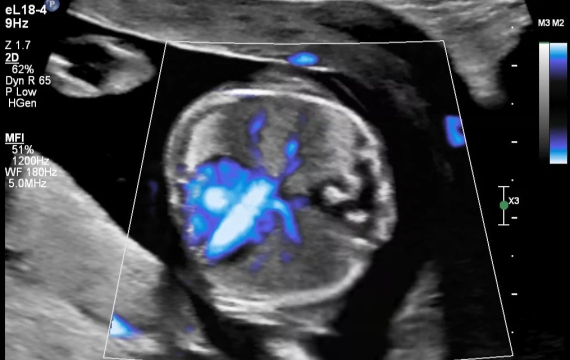

El escáner de ultrasonido Philips Affiniti 70 es un dispositivo de imágenes de próxima generación que ofrece una amplia gama de funciones y capacidades. Con sus modos de imágenes avanzados, incluidos el modo B, el modo M y el Doppler, este escáner ofrece imágenes de alta calidad para un diagnóstico preciso.

Además, el modelo Affiniti 70 tiene características únicas e innovadoras que lo diferencian de otros ecógrafos. Por ejemplo, la tecnología PureWave mejora la nitidez y la resolución de la imagen, lo que permite una mejor visualización de las estructuras anatómicas.

El ecógrafo Affiniti 70 tiene una amplia gama de aplicaciones en radiología. Se puede utilizar para obtener imágenes de varios órganos y sistemas, incluidos el abdomen, la pelvis, el sistema musculoesquelético y las estructuras vasculares. Las imágenes de alta calidad producidas por los radiólogos del escáner ayudan a realizar un diagnóstico muy preciso y producen mejores resultados para los pacientes.

El Affiniti 70 puede crear imágenes abdominales de alta resolución que ayudan a los radiólogos a detectar anomalías como cálculos biliares o tumores. Las capacidades del escáner desempeñan un papel crucial en el diagnóstico preciso.